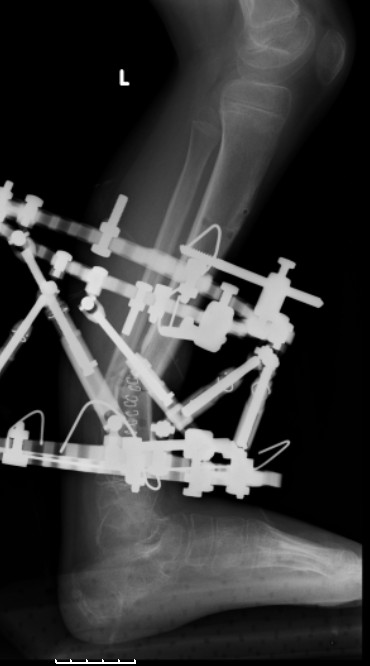

3,4 - через 4 недели наложен спице-стержневой аппарат, произведена остеотомия большеберцовой кости в верхней трети, раны зажили, проводилась дистракция в аппарате.